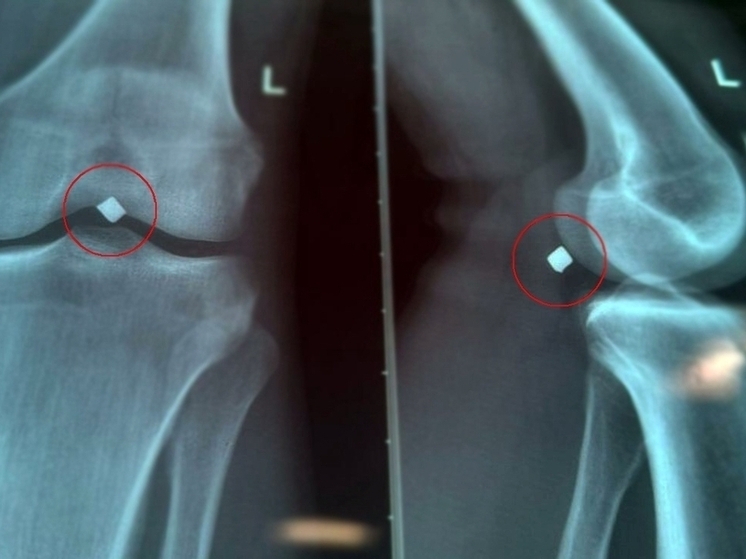

В больницу обратился 22-летний молодой человек, в июне этого года он получивший ранение осколком. Осколок пробил надколенник насквозь, прошел через полость коленного сустава и застрял в паре миллиметров от крупного сосудисто-нервного пучка.

«Провели обследование, рентген показал местонахождение осколка. Во время вмешательства выяснилось, что осколок лежал прямо на стенке подколенной вены и практически пролабировал ее, создавая прямую угрозу жизнеугрожающего кровотечения», — рассказал сердечно-сосудистый хирург Вячеслав Карпов.